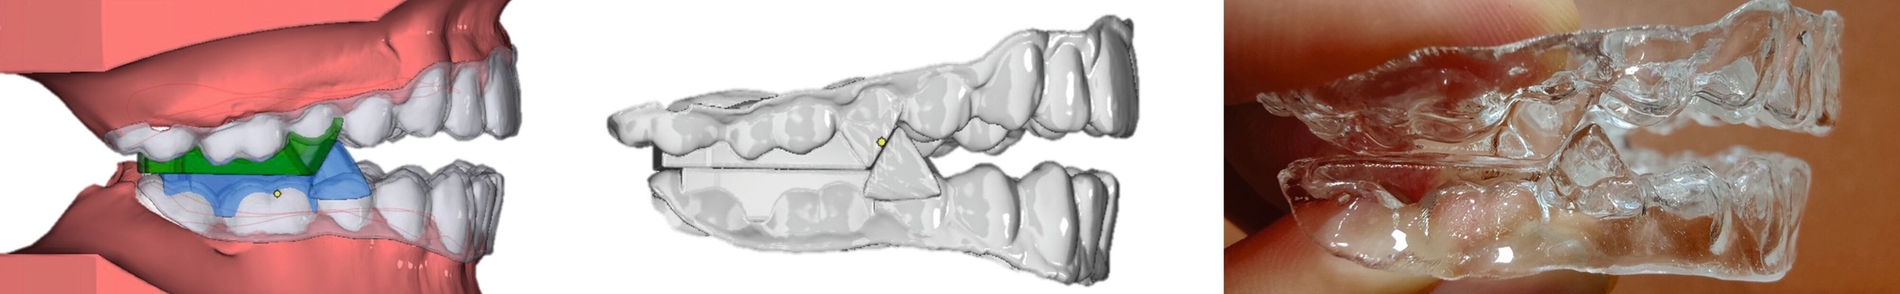

Aligner

Unter den digital gefertigten kieferorthopädischen Apparaturen sind Aligner wohl das bekannteste Beispiel [Ercoli et al., 2014, Robertson et al., 2020]. Die Herstellung von Alignern selbst basiert(e) jedoch auf einer manuellen Fertigung anhand 3-D-gedruckter Modelle und stellt(e) somit bisher eher eine partiell automatisierte Fertigung dar. Die neuesten Entwicklungen erlauben mittlerweile eine Fertigung im direkten 3-D-Druckverfahren [Tartaglia et al., 2021], so dass mühsame, zeitaufwendige Zwischenschritte der manuellen Fertigung entfallen (Abbildung 1a). Weiter profitieren die Patienten von individuelleren Fertigungsmöglichkeiten, da durch die Umsetzung im 3-D-Druck zusätzliche Elemente einfacher und stabiler in den Aligner inkorporiert werden können (Abbildung 1b).